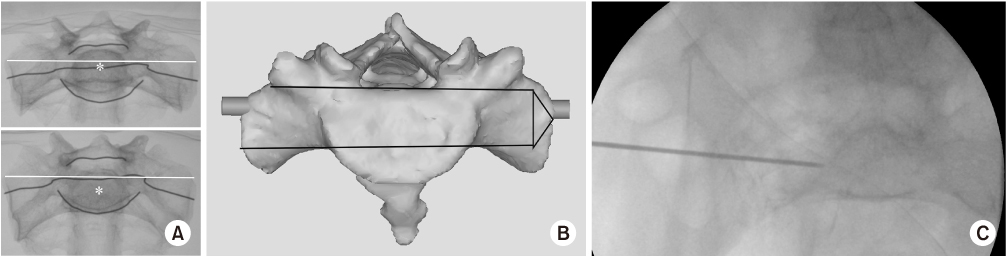

Fig. 9

(A–C) S2 alar-iliac (S2AI) screw should be toward the AIIS and passed just over the superior rim of the greater sciatic notch, above the greater sciatic notch. (D) The screw trajectory was from the dorsal cortex of the sacrum to the inner ilium by penetrating the sacro-iliac joint.